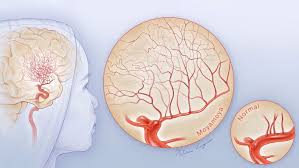

모야모야병(Moyamoya Disease)은 뇌의 주요 혈관인 내경동맥이 점차 좁아지거나 막혀, 뇌로 가는 혈류가 줄어들고, 이를 보상하기 위해 뇌 안에 가느다란 새로운 혈관이 형성되는 희귀 질환입니다. 이 혈관들은 뇌혈관조영술 영상에서 연기처럼 퍼지는 모습으로 보이는데, 일본어로 ‘모야모야’(もやもや)는 안개가 자욱한 모양을 의미합니다. 이러한 특이한 혈관 소견 때문에 ‘모야모야병’이라는 명칭이 붙었습니다. 주로 "소아기와 청장년기(20~40대)"에 발생하며, 뇌출혈, 뇌경색, 일과성 허혈 발작 등을 유발할 수 있어 조기 발견과 치료가 매우 중요합니다.

③ 뇌혈관조영술(DSA)

- 진단의 골드 스탠다드

- 정맥 또는 동맥에 조영제를 주입한 후 뇌 전체 혈관망을 실시간으로 촬영

- 모야모야 혈관의 특성적인 모습(연기처럼 퍼짐)을 확인할 수 있음